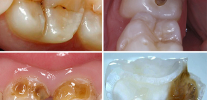

La foto sotto mostra un esempio di carie profonde, in cui la camera pulpare del dente è già molto probabilmente interessata: